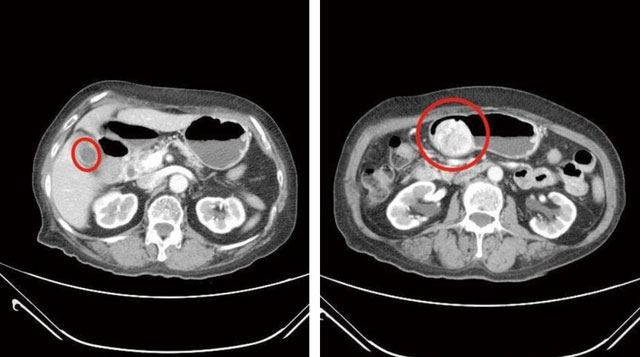

Sau khi nội soi tiêu hóa trên và chụp CT, các bác sĩ phát hiện cùng lúc bà gặp phải 2 vấn đề nghiêm trọng trong ổ bụng. Một là sỏi chất đầy trong túi mật và hai là khối u dạ dày loại mô đệm đường tiêu hóa 6cm. Điều đáng nói là khối u này không phải mới xuất hiện mà đã được nghi ngờ từ 3 năm trước nhưng bà Lin không chịu thăm khám chuyên sâu, cũng cho rằng không có triệu chứng khó chịu rõ ràng.

Ngay sau đó, bà được phẫu thuật loại bỏ sỏi túi mật và cắt bỏ khối u. Hiện tại đang được chăm sóc hậu phẫu và chuẩn bị điều trị khối u bổ sung theo phác đồ từ bác sĩ.